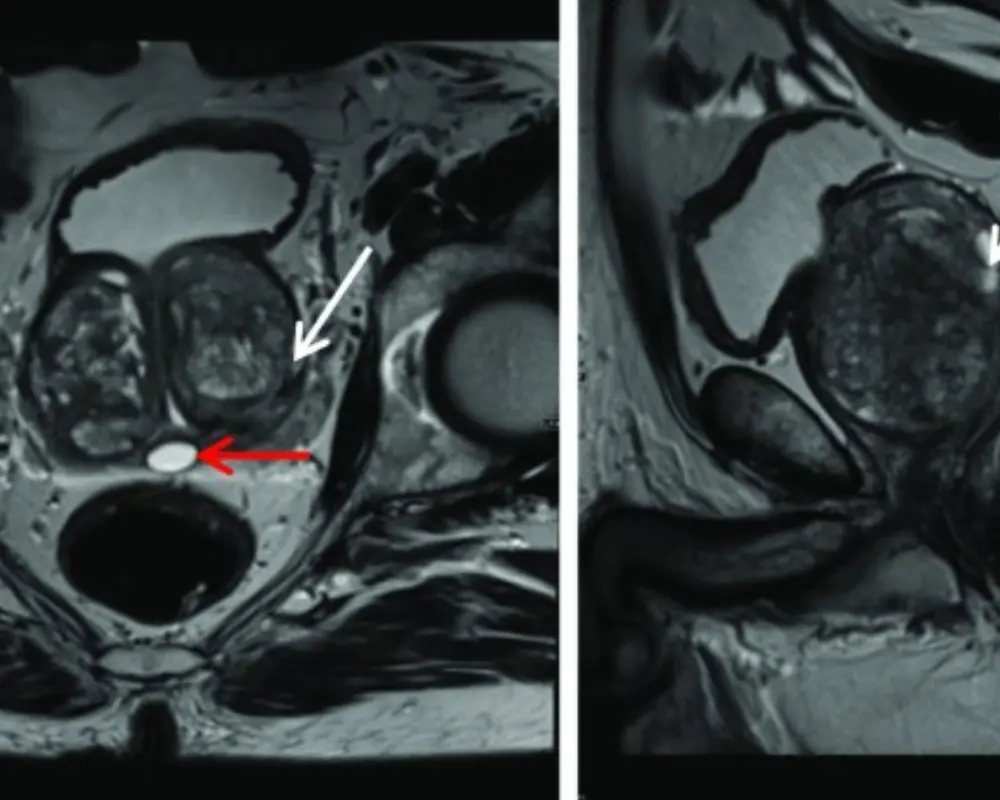

Each prostate MRI scan is performed using advanced imaging techniques designed to capture clear detail in a small and sensitive area of the body. In some cases, your provider may request an MRI of Prostate in Houston TX with contrast to highlight specific areas more clearly. This imaging is commonly used to guide biopsy decisions, assess known findings, or monitor changes over time. Whether you are visiting from Houston or nearby areas including Richmond, the goal is to provide clear results that support confident and timely care decisions.

Prostate MRI helps identify areas linked to prostate cancer. It shows suspicious regions and supports early detection when further testing is needed.

Prostate MRI helps assess if cancer has spread beyond the prostate. It gives important detail that helps guide treatment planning and next steps.